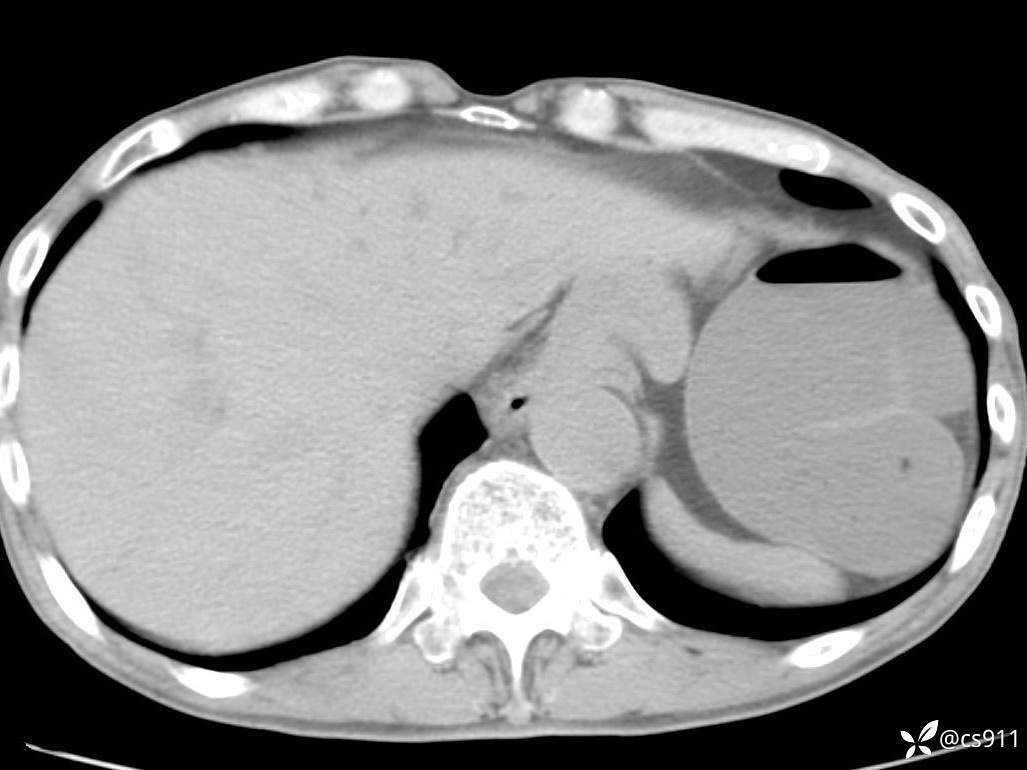

急腹症之急诊CT,原因?答案公布

男,77岁,腹痛、腹胀伴恶心呕吐1天。呕吐胃内容物,非喷射性呕吐,有咖啡色样胃内容物,诉有胃穿孔病史。查体:全腹平,下腹部压痛,全腹无反跳痛,叩诊呈浊音,移动性浊音阴性,肠鸣音减弱,1-2次/分。肛检:直肠未扪及明显肿物,可触及大量粪块。

血淀粉酶(AMY) HH 1859 U/L 35-135